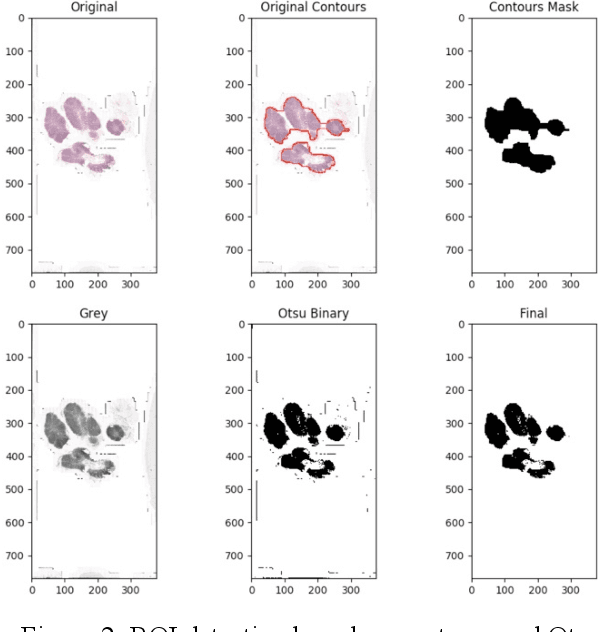

Detection and Classification of Breast Cancer Metastates Based on U-Net

Sep 09, 2019

This paper presents U-net based breast cancer metastases detection and classification in lymph nodes, as well as patient-level classification based on metastases detection. The whole pipeline can be divided into five steps: preprocessing and data argumentation, patch-based segmentation, post processing, slide-level classification, and patient-level classification. In order to reduce overfitting and speedup convergence, we applied batch normalization and dropout into U-Net. The final Kappa score reaches 0.902 on training data.